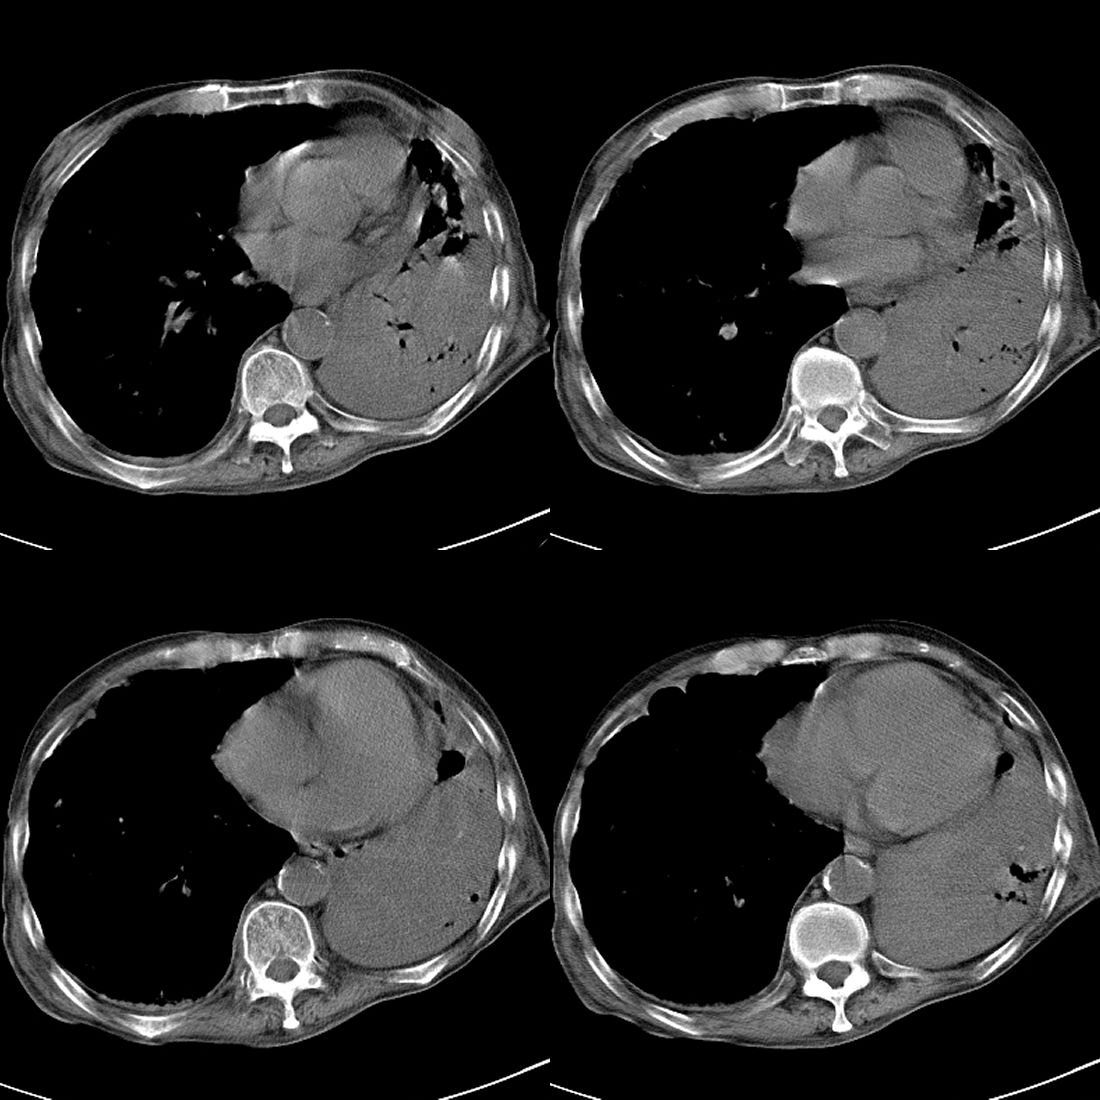

以下是引用liuyue在2008-11-30 6:01:00的发言:[br]双肺继发性肺结核;左侧包裹性积液;建议增强化或支气管镜检查除外左肺占位性病变.

以下是引用吴承学在2008-11-30 8:02:00的发言:[br]双肺继发性肺结核;左侧包裹性积液;建议增强化或支气管镜检查除外左肺占位性病变.[br]